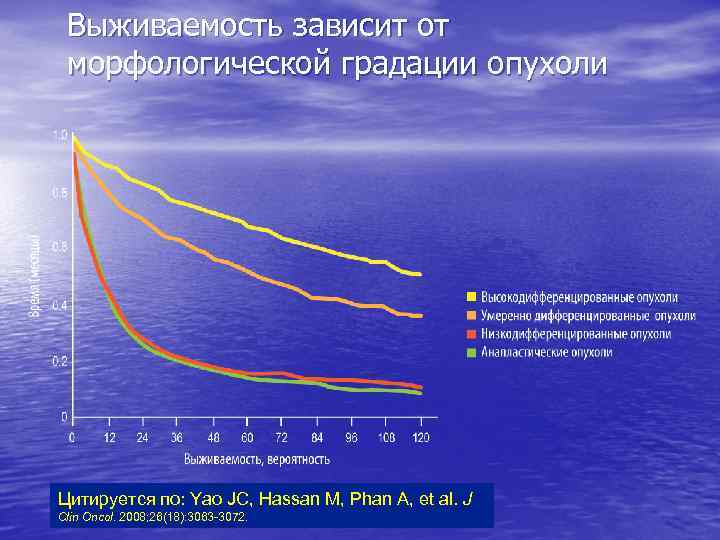

Выживаемость зависит от морфологической градации опухоли Цитируется по: Yao JC, Hassan M, Phan A, et al. J Clin Oncol. 2008; 26(18): 3063 -3072.